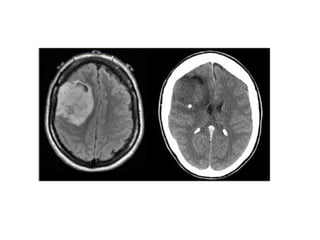

• Neuroimaging:

– CT and MRI methods appear to be equally sensitive.

– CT Scan: Intracranial Hemorrhages.

– MRI: Useful for posterior fossa and temporal lobe.

Investigations: • CBC- Whensystemic or intracranial infection suspected. • Neuroimaging: – CT and MRI methods appear to be equally sensitive. – CT Scan: Intracranial Hemorrhages. – MRI: Useful for posterior fossa and temporal lobe. • Lumbar Puncture: CSF fluid analysis.